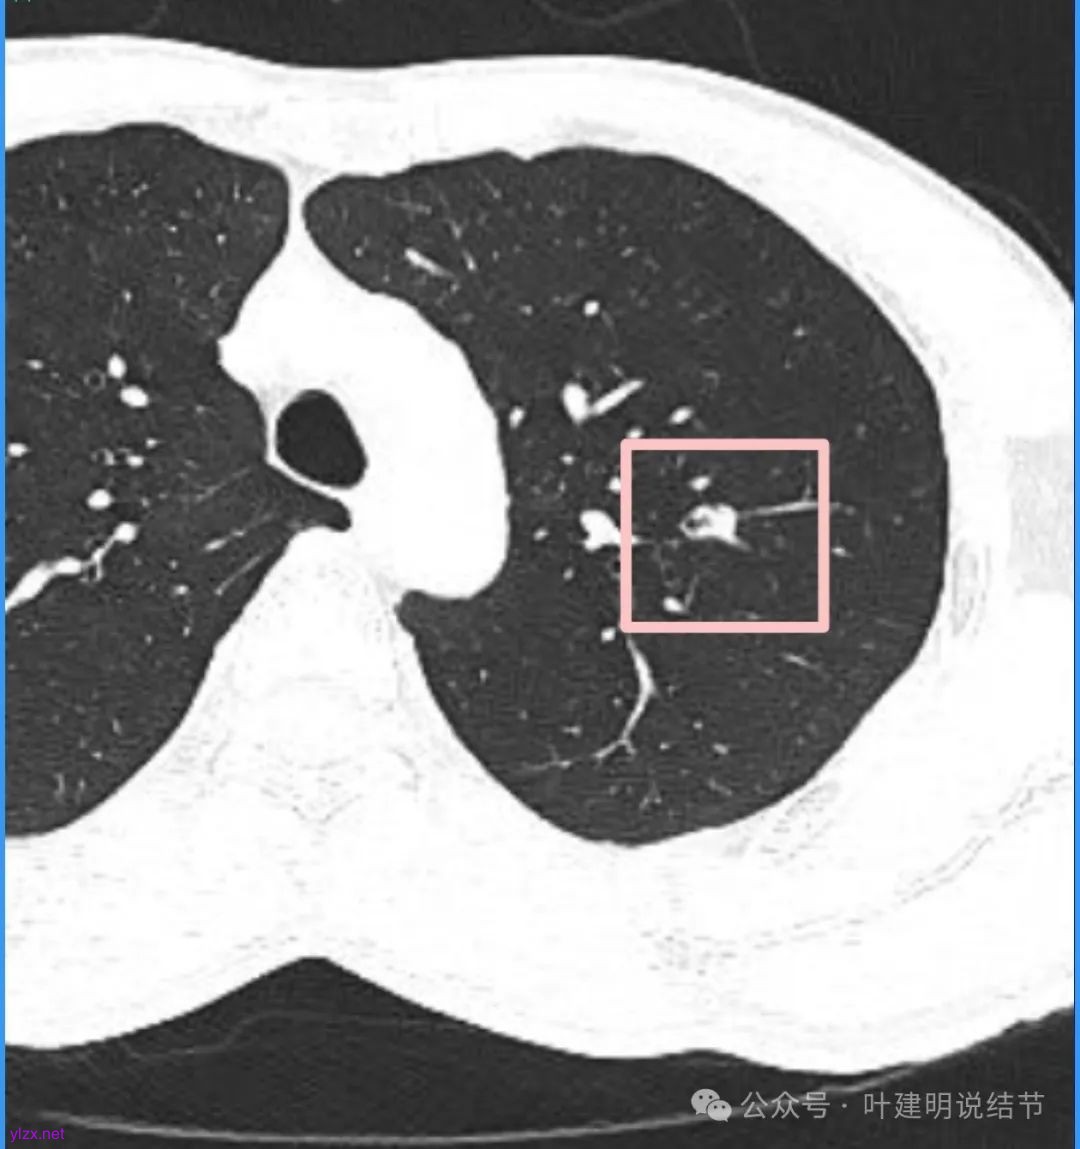

再看看近半年前2024年11月时的影像:

我们发现一是病灶与25年3月的几乎没有区别,二是原来蓝色箭头处不太像血管,而是结节边缘的一部分,而结节灶内又是有扩张支气管的。

左肺上叶这个病灶总体上来讲2025年3月的与2024年11月份相比没有显著进展。我们逐层从细节上去分析,会发现:1、病灶开始出现的层面就有临近的支气管扭曲变形,这些人用肿瘤导致的牵拉不能解释,反而用细支气管扩张伴慢性炎容易解释;2、病灶内部仍然多个层面都有见到扩张的细支气管,可是如果是肿瘤,与导致细支气管扩张相应的病灶本身的收缩力或者边缘毛刺又不明显;3、病灶边缘基本上都比较光滑平直,没有像外周浸润性生长的枫叶或者毛刺;4、虽然有血管贴边或者进入,但是说不上显著的血管异常增粗;5、整体来讲病灶实性成分密度过高,随访对比进展不明显,用结节是恶性不太能够解释相应的影像表现,所以我倾向于考虑是细支气管扩张伴有周围慢性炎或者肉芽肿性炎。至少从风险高低的角度来看,几个月的间隔没有明显进展的情况下加上位置又不好,如果手术需要切除范围比较多,所以应该在随访观察比较稳妥,可以考虑半年复查对比。意见供参考!